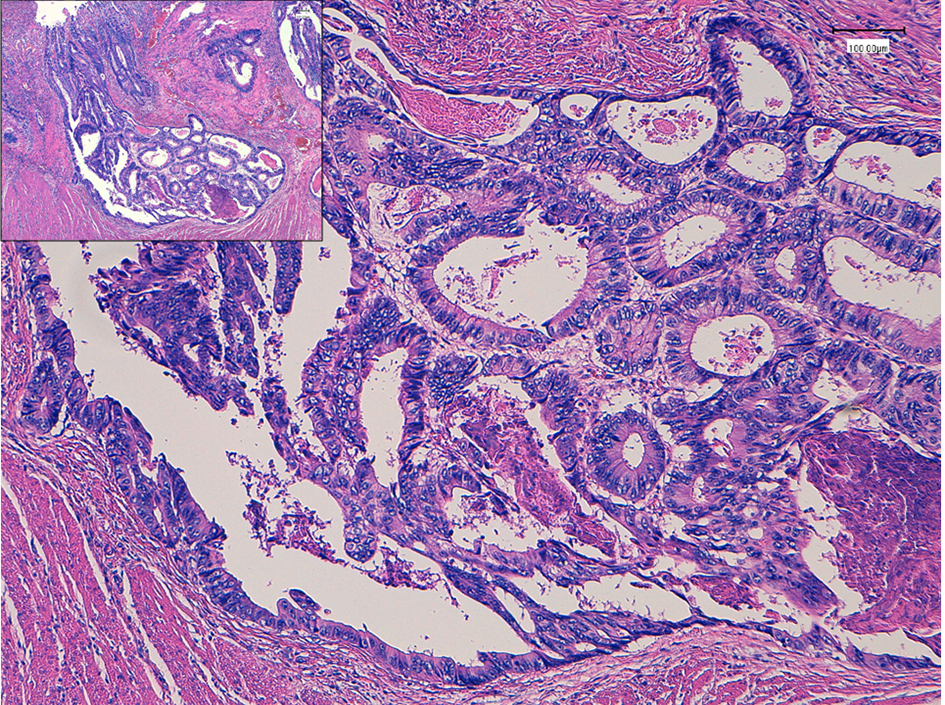

Seven years ago, a 51-year-old Japanese man received sigmoidectomy for the treatment of sigmoid colon cancer (stage I). It was histopathologically moderately differentiated adenocarcinoma (tub2, Fig. 1). He was intensively followed up after the operation. He was well controlled for his diabetes mellitus in Department of General Medicine of our hospital. On November 16, 2015, slight elevation of serum enzymes, alkaline phosphatase (ALP, 352 IU/L; normal range, 104 - 338 IU/L) and γ-glutamyltransferase (γ-GT, 160 IU/L; normal range, 0 - 47 IU/L) of hepatobiliary system was noted. A tumor marker, CEA (5.2 ng/mL; normal range, 0 - 4.9 ng/mL), was slightly elevated. Follow-up CT (Fig. 2a) and MRI (Fig. 2b) examinations revealed dilatation of small intrahepatic bile duct in the S5/6 area, suggesting intrahepatic cholangiocarcinoma or metastatic tumorous lesion. Clinical diagnosis based on the image analysis was intrahepatic cholangiocarcinoma or liver metastasis of CRC.

![]() Click for large image | Figure 1. Histopathology of colon cancer, which was observed in the sigmoid colon 7 years ago. Moderately differentiated adenocarcinoma (tub2) invaded into the muscular layer. Insert is a low power of view. Bars, 100 μm. Hematoxylin and eosin stain. |